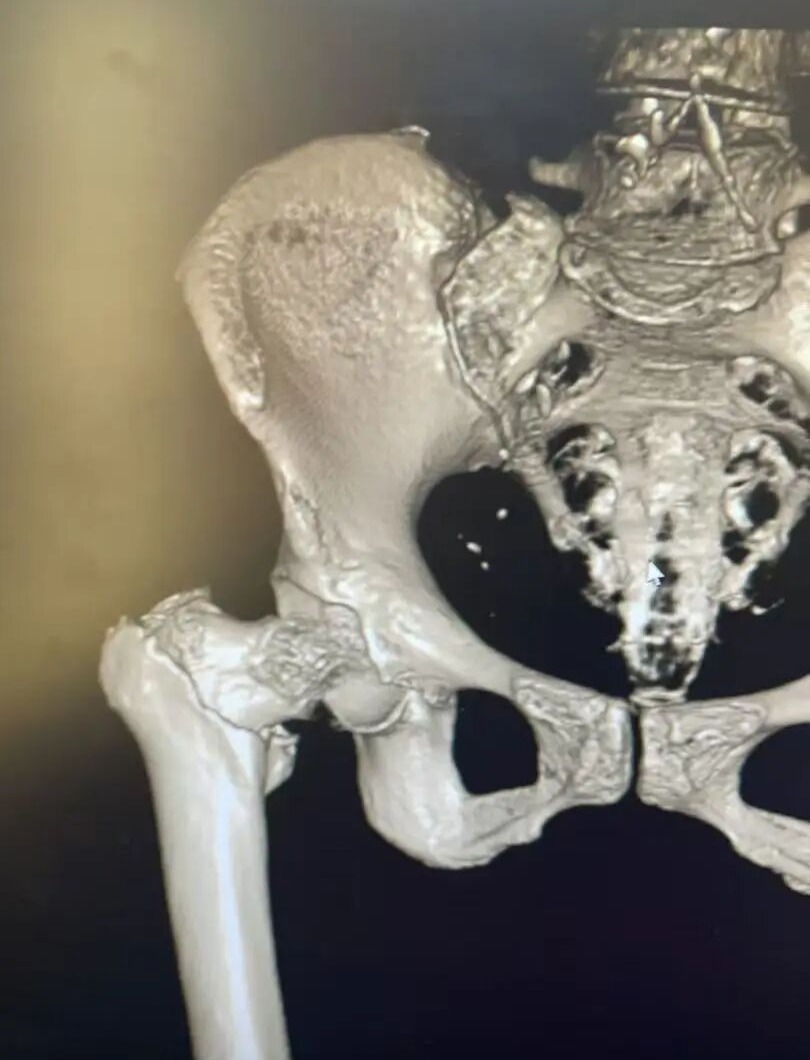

患者术前影像

入院后,急诊科迅速为陈大爷 开通绿色通道 ,第一时间完善各项检查。CT结果显示:左侧股骨大粗隆粉碎性骨折,伴局部碎裂骨片分离错位。考虑到陈大爷 年事已高,且基础疾病较多, 骨科团队迅速行动,组织内科、麻醉科等 多学科专家进行会诊评估讨论 。经过全面、细致的分析,最终确定 闭合复位PFNA内固定术为首选治疗方案 。